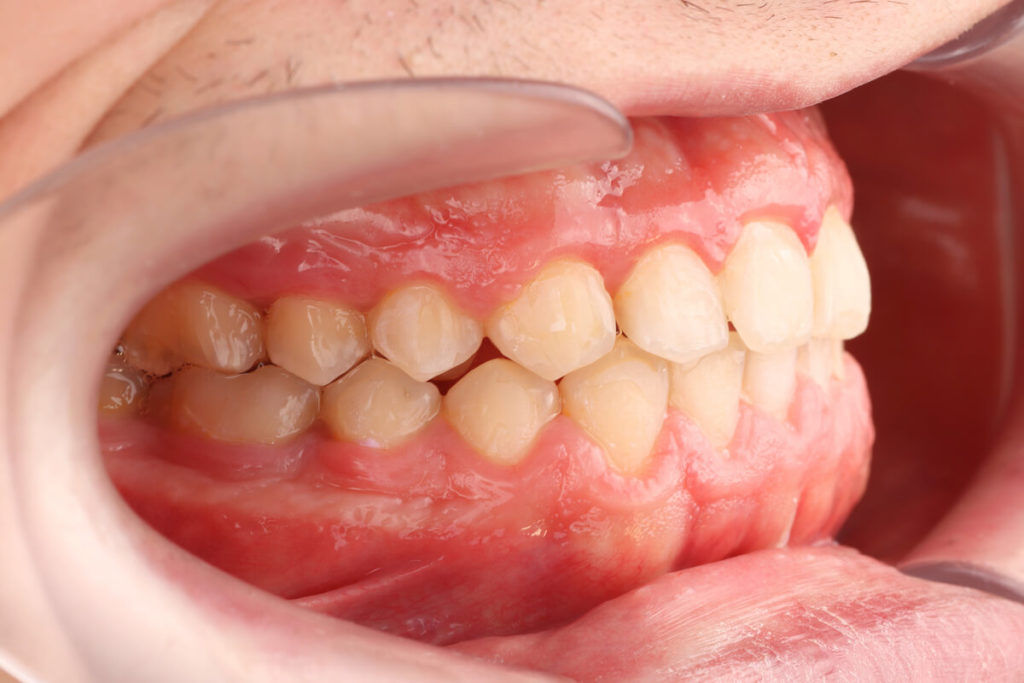

SITUACIÓN INICIAL

CLASE I MORDIDA CRUZADA EN LATERALES

• Clase I con mordida cruzada en los incisivos laterales.

• Apiñamiento moderado en el arco superior e inferior.

• Desplazamiento de la línea media superior.

• Arco normal con necesidad de expansión.